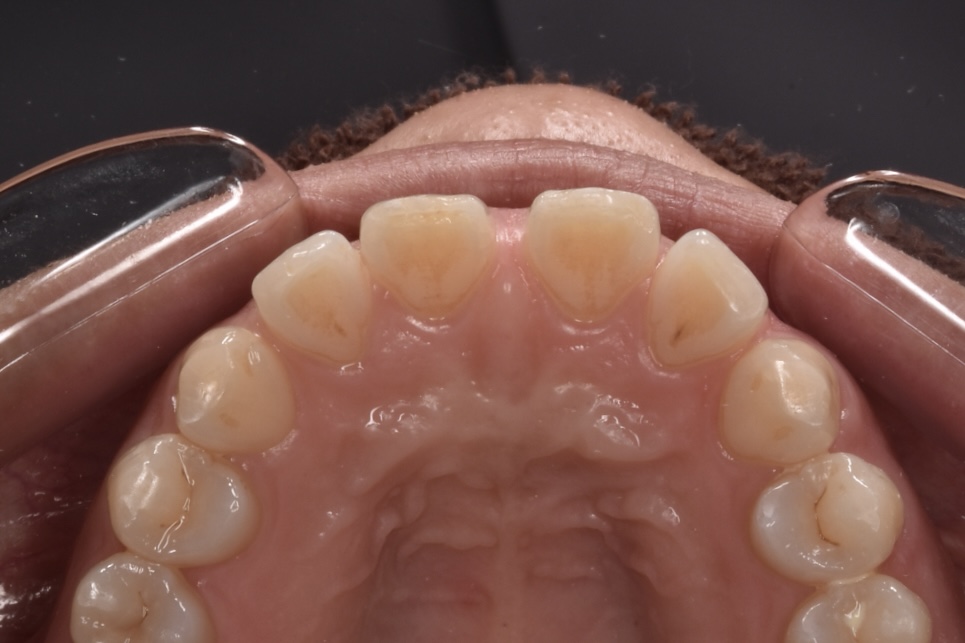

すきっ歯の改善を矯正治療でおこなった例です

モニター1 インビザラインライトプランで治療 治療期間14週間(約3・5ヶ月)

治療前